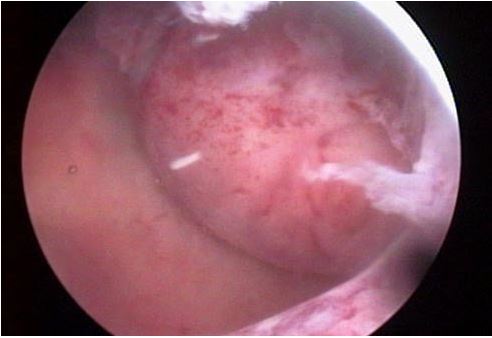

一根導管 被導入 子宮動脈,然後

很 微小的 塑料製品或 凝膠通過 導管釋 放 進入血管,

從而使 肌瘤 在一段時間 以後 縮小。